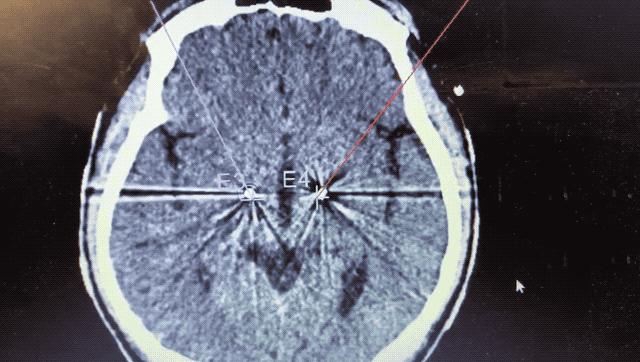

順利檢測到典型的核團(tuán)信號后,再次植入刺激電極到相應(yīng)位置,測試后即可完成單側(cè)的電極植入。對側(cè)只需借助機(jī)器人再次定位,并將檢測電極、刺激電極依次植入,最后,還需將刺激器植入患者胸前皮下。根據(jù)術(shù)后CT顯示,本手術(shù)雙側(cè)植入電極的位置與術(shù)前規(guī)劃路徑完全吻合,患者開機(jī)后,起搏器會開始沿刺激電極向患者核團(tuán)實(shí)施高頻電刺激,以減輕疾病癥狀,提高患者的生活質(zhì)量。

alt text

術(shù)后CT顯示雙側(cè)電極植入位置與規(guī)劃完全吻合